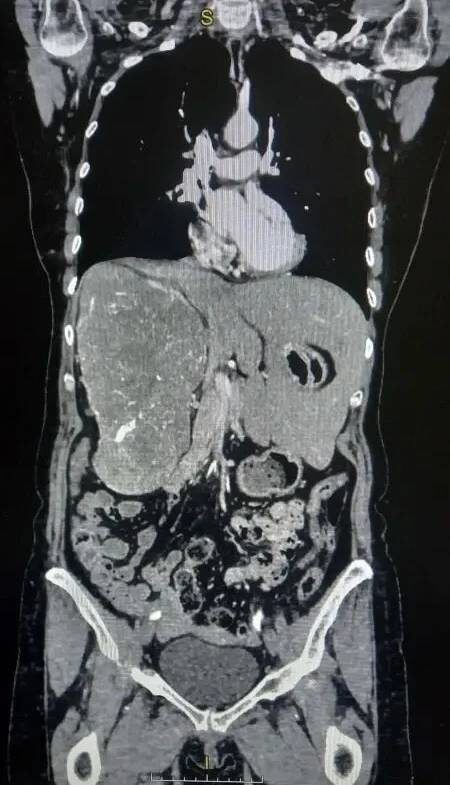

Пациентка долго жаловалась на боли в пояснице и тяжесть в животе. Компьютерная томография с контрастированием показала, что опухоль почти полностью заняла правую половину брюшной полости и сместила печень. Правая почка почти не функционировала, о чем свидетельствовали результаты обследования. Размер опухоли составил 16,5х11,5х21,1 см.

Как сообщает областной комитет здравоохранения, хирурги Волгоградского областного онкологического диспансера (ГБУЗ ВОКОД) провели редкую операцию на почке, где столкнулись с необычной анатомией: гигантская опухоль фактически сместила жизненно важные органы. Печень пациентки была полностью перемещена из правой стороны живота в левую.

Несмотря на риски, заведующим ООХМЛ4 было принято решение провести оперативное лечение. Пациентка была госпитализирована и подготовлена к операции, которая не могла быть выполнена лапароскопически из-за большого размера опухоли. В феврале 2026 года была проведена радикальная нефрэктомия справа. Операцию проводил заведующий ООХМЛ4 (онко-урология) врач высшей категории Проноза В.В., ассистировал врач Алейников А.А. После операции все прошло без осложнений. Контрольное УЗИ ОБП показало отсутствие проблем в области операции и в брюшной полости, анализы также были в норме. Гистология подтвердила наличие светлоклеточной карциномы, но опухоль не прорастала в соседние органы, а только отдавливала, что позволило провести успешную операцию. Пациентка выписана через 8 дней после операции под наблюдение врачей.